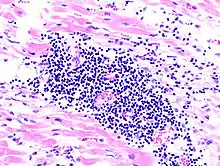

Virale Myokarditis

Ät.: Coxsackie-, ECHO-, Adenoviren, Influenzaviren

Pathogenese: Herzmuskelnekrose durch Virus und T-Zell-vermittelte Immunreaktion.

Mikro: Interstitielles lymphozytäres Infiltrat (kleine blaue Zellen), kaum Nekrosen.

![]() idem. |